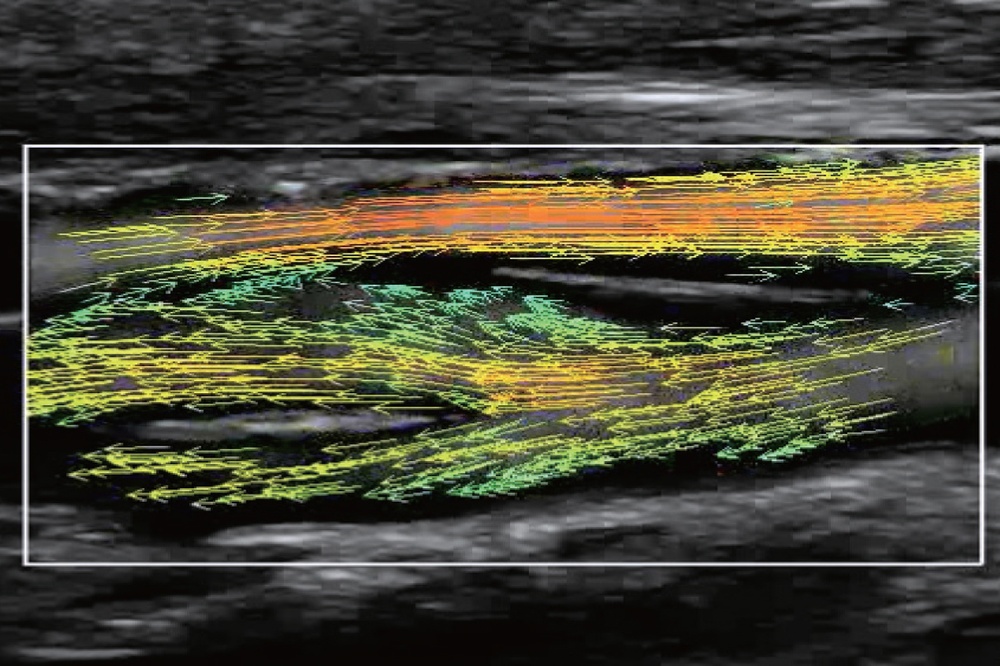

Метод визуализации интуитивно понятен и состоит из массива цветных стрелок, которые демонстрируют скорость и направление движения частиц крови.

На изображениях, приведенных ниже показаны примеры из клинической практики врачей ультразвуковой диагностики, полученные в процессе апробирования прибора Mindray Resona 7. Приводится наглядные примеры сравнения традиционного режима ЦДК и режима V Flow (Vector Flow).

Изображен ламинарный поток сонной артерии. В режиме ЦДК отсутствует информация о профиле ламинарного потока. Режим V Flow визуализирует не только скоростные характеристики с помощью цветных стрелок, но и предоставляет данные о профиле ламинарного потока (быстрый поток в центре и медленный вблизи стенок сосуда).

Изображена яремная вена и бифуркация сонной артерии. CAA, ICA и ECA показаны на одном изображении. В режиме ЦДК отсутствует подробная гемодинамика. В режиме V Flow отображаются данные о скорости и направлении движения частиц крови во всей зоны интереса, включая изменения характеристик кровотока в сонной артерии и яремной вене.